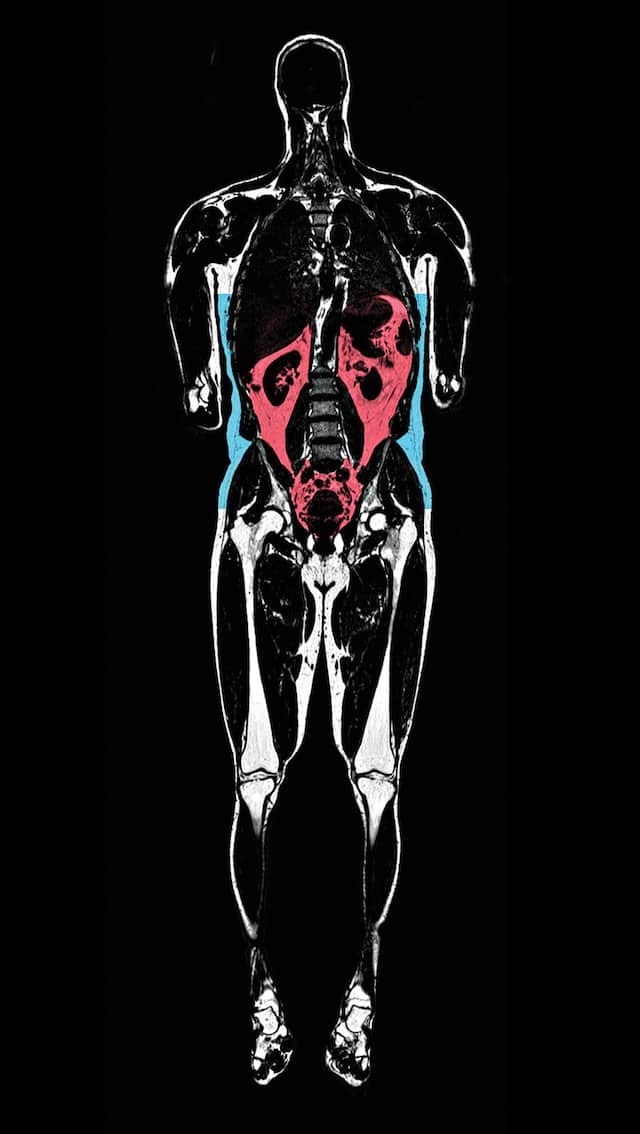

MRIs performed on some Biobank participants create 3D images that show subcutaneous fat under the skin in blue and visceral fat around the organs in red. Visceral fat has been linked to diseases. (See graphic below.)

AMRA MEDICAL AB

IT’S NOT THE FAT—

IT’S WHERE IT’S AT

Body mass index (BMI) has long been used to

measure obesity and health risk, yet it can’t

explain why an overweight person might be

healthy or why a seemingly healthy person

might get heart disease or diabetes. New MRI

data show that when it comes to fat, where it’s

located matters most.

FAT DISTRIBUTION

Subcutaneous fat, under the skin, can be less

harmful than visceral fat, found around the or-

gans. Visceral, liver, and muscle fat (orange

lines, below) are linked to metabolic diseases.

Subcutaneous

Visceral

Obese

Four women with

a BMI of 32 but

different fat

distribution

Normal weight

Four women with a

BMI of 24 but differ-

ent fat distribution

Probability of:

High

Heart disease:

Type 2 diabetes:

Metabolic disease:

Low